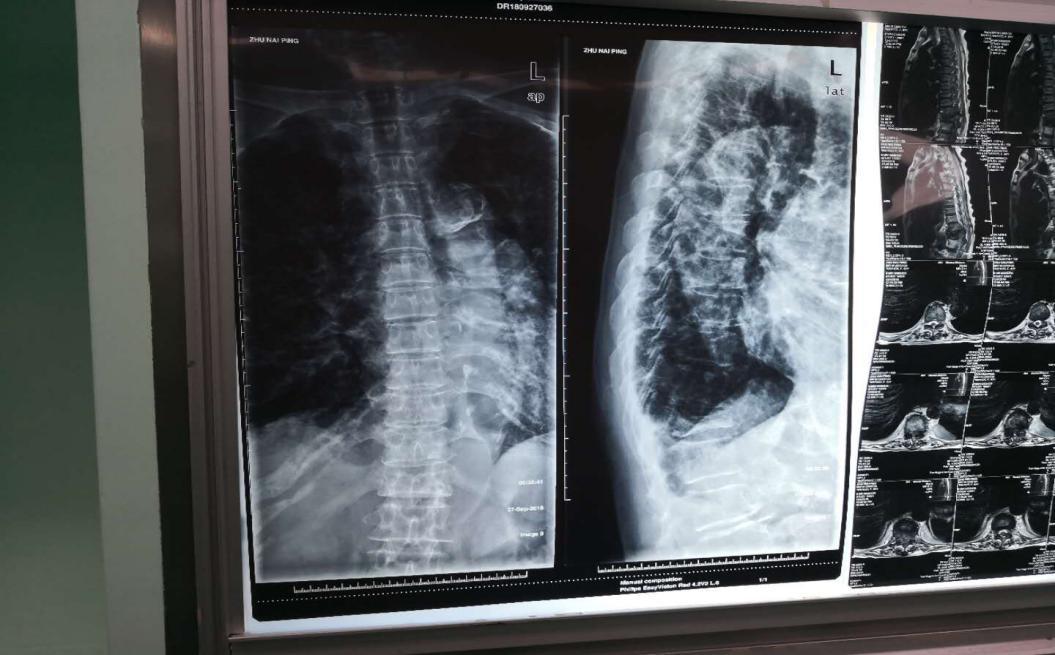

近日,一位84岁的患者到乌海市人民医院骨二科就诊,两月前在老人不慎摔倒,经检查为胸十二椎体压缩性骨折,需手术治疗,但是患者选择了回家保守治疗。日前患者在家独自上卫生间时再次跌倒导致双腿无法行走站立。经核磁检查后诊断为胸十二椎体压缩性骨折伴不完全瘫痪,骨折块已经压迫到了腰椎神经。

刘涛主任医师和其他医生在综合各种因素后,决定为患者实施“椎板减压骨水泥钉椎弓根系统内固定术”。术后患者的症状明显改善,双下肢肌力善为4级。此例骨水泥钉术为乌海市首例,手术的成功也填补了乌海市在此技术领域的空白。此项手术技术的开展,对于老年人、骨质疏松等患者具有显著意义,缩短了术后恢复时间,减轻了家庭负担。